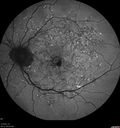

65 year old woman with gradually declining central vision. VA 20/200 in both eyes in the later photos (left eye was better in earlier photos). FAF shows pisciform tri-radiate lesions that are hyper FAF typical of stargardt's fundus flavimaculatus

Stargardt's Macular Dystrophy ABCA4 positivevaatamisi: 536 Fundus Autofluorescence shows central atrophy with Hyper FAF pisciform triradiate lesions. Images show some progression over 3 years of macular dystrophy.00000